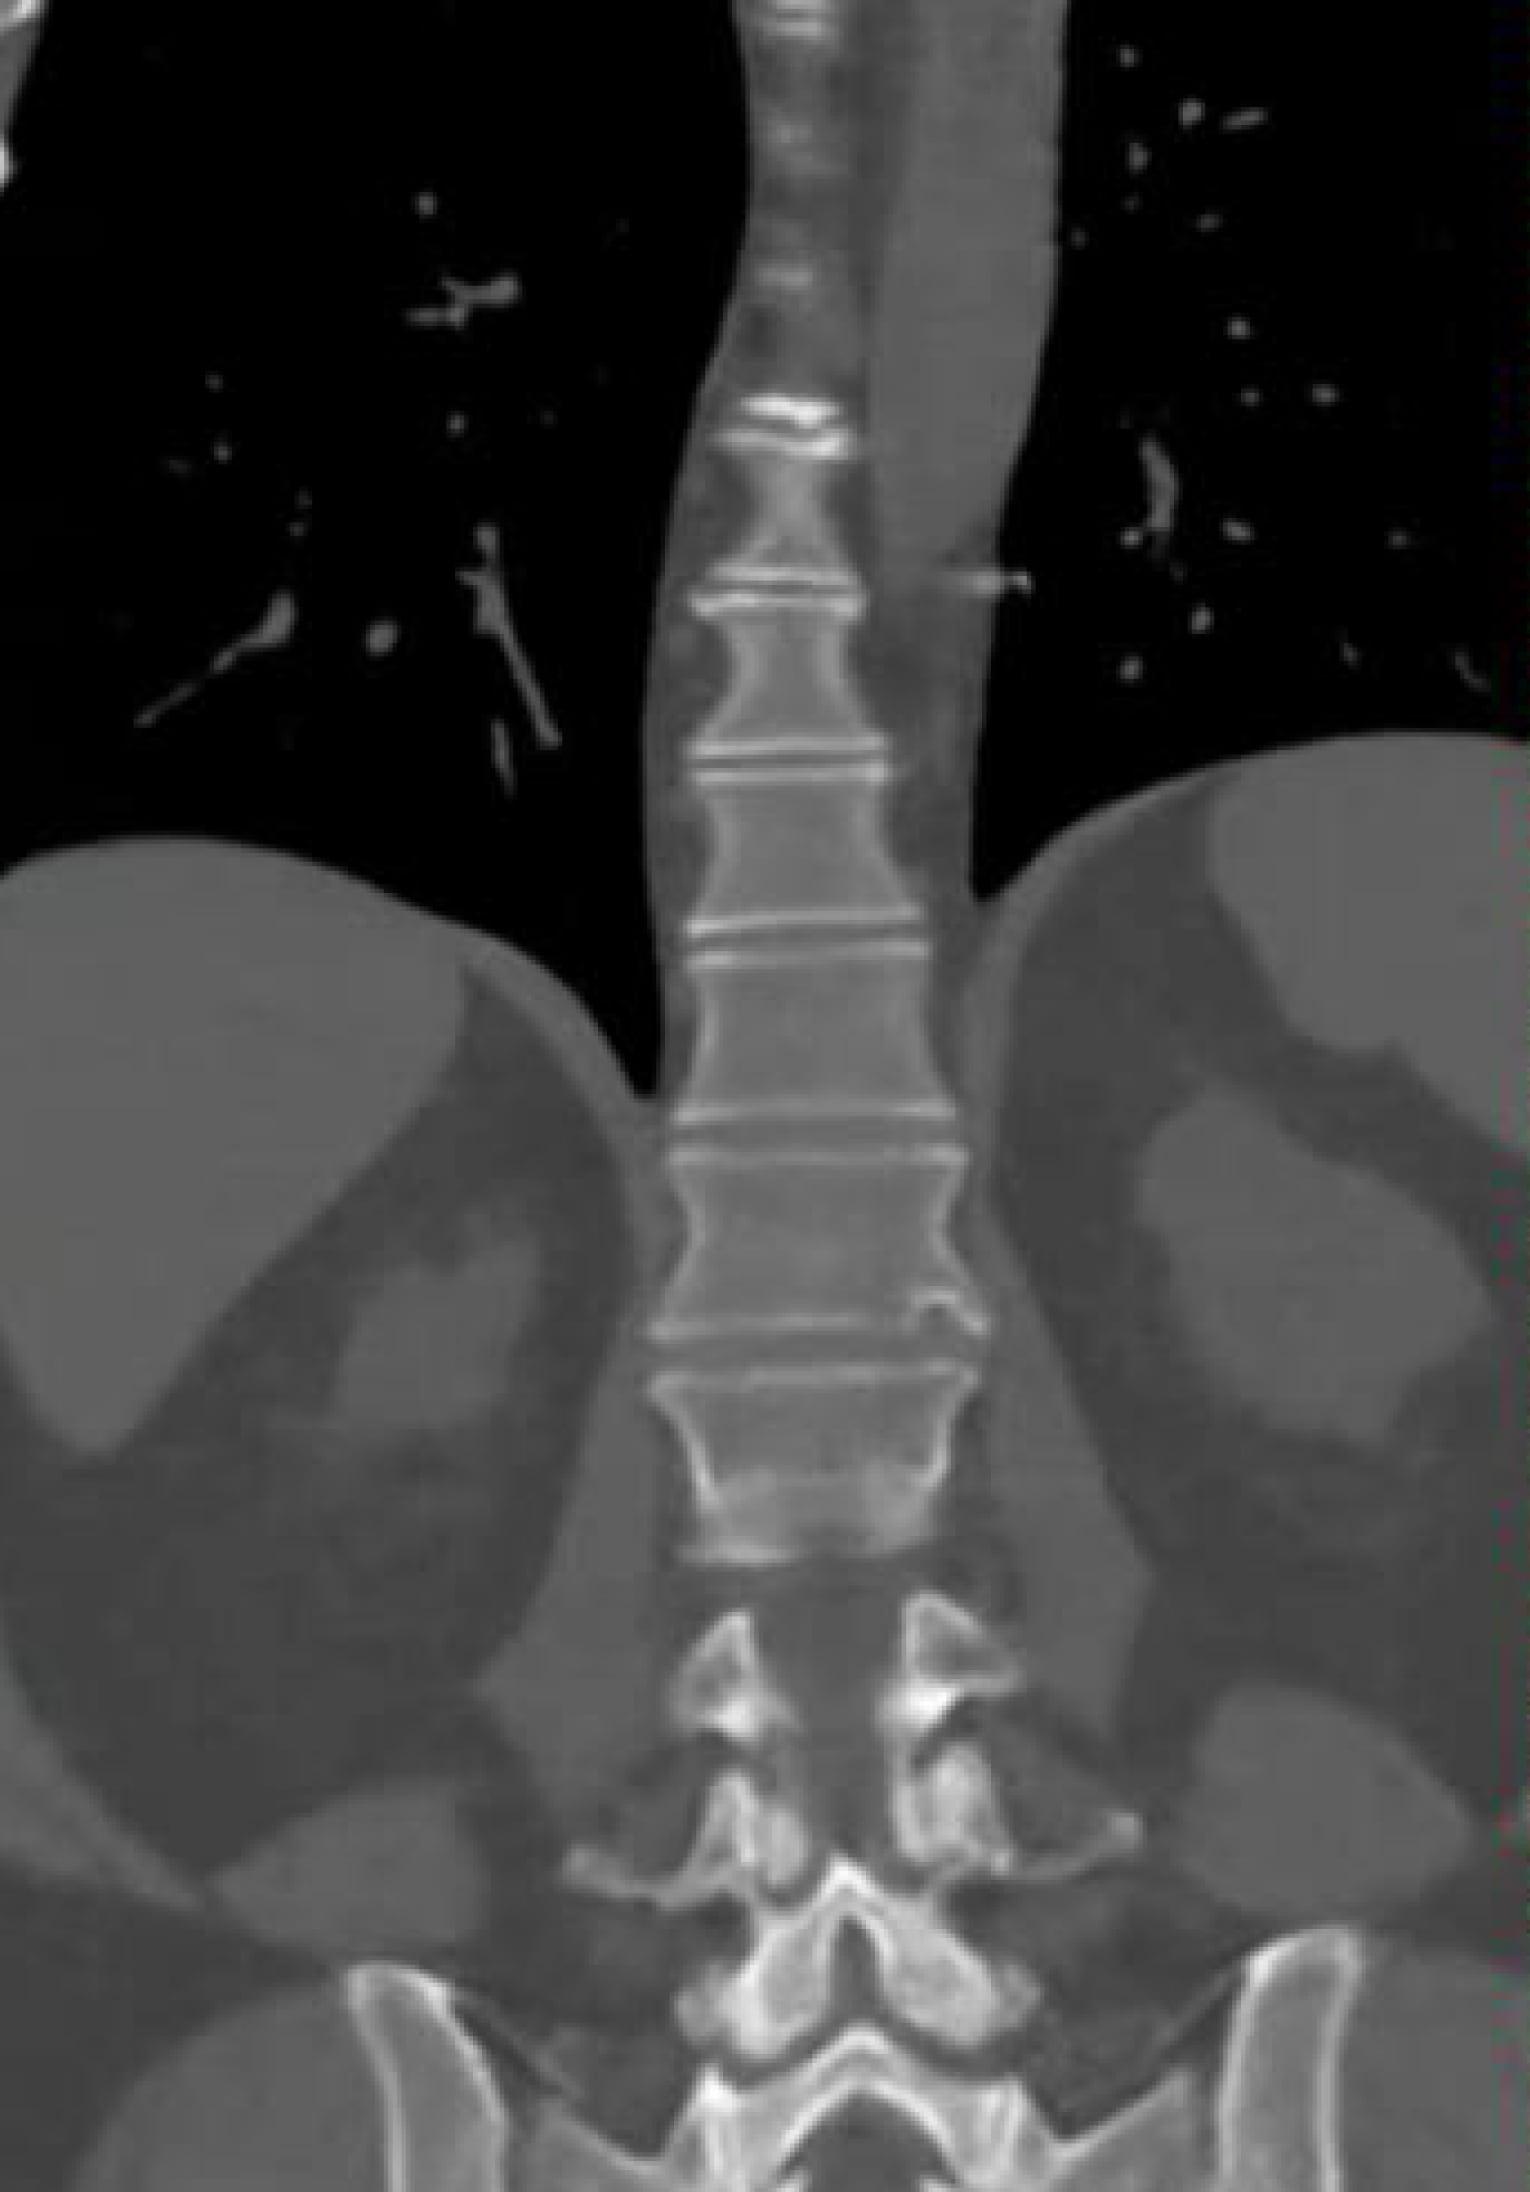

Neueste Technologie in der intraoperativen Bildgebung

Diese Methode ist insbesondere bei komplexen Operationen von großem Vorteil, da sie eine genauere Überwachung des chirurgischen Eingriffs ermöglicht. Zudem können im Verlauf der Operation wichtige Informationen und Daten erhoben werden, die für die weitere Behandlung von großer Bedeutung sind.